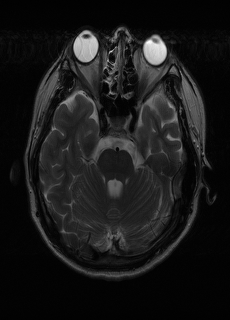

As we observe from the right image in Fig. 2, our BRM, both from MIMO and SISO settings, predicts the performance of dedicated models with a high correlation. We further choose the best three , and perform the last stage of fine-tuning accordingly to (6). A visual evaluation on real data is shown in Fig. 3. For simulated data, please refer to the Supplemental Material section.

Base on the best performing , we perceive that among , , and FLAIR, the results are best when is sampled the most. We suggest that this makes intuitive sense as images provide the best contrast out of the three sequences, which can compensate for the details lost in other images. The same observation can be made on the simulated data, where both and FLAIR show good contrast. When the time setting is changed to non-uniformity, we can see that our search for the best sampling strategy reflects the change. is sampled more as a result of faster acquisition time, while is still sufficiently sampled.

| Sequence | LR | SISO | MIMO | MIMO tuned | GT |

|---|---|---|---|---|---|

(a) 34.38/0.9371

(a) 34.38/0.9371

|

(b) 42.42/0.9883

(b) 42.42/0.9883

|

(c) 44.60/0.9920

(c) 44.60/0.9920

|

(d) 45.50/0.9940

(d) 45.50/0.9940

|

(e) PSNR/SSIM

(e) PSNR/SSIM

|

|

(f) 29.74/0.8903

(f) 29.74/0.8903

|

(g) 36.25/0.9734

(g) 36.25/0.9734

|

(h) 36.42/0.9752

(h) 36.42/0.9752

|

(i) 37.70/0.9832

(i) 37.70/0.9832

|

(j) PSNR/SSIM

(j) PSNR/SSIM

|

|

(k) 39.89/0.9311

(k) 39.89/0.9311

|

(l) 43.94/0.9864

(l) 43.94/0.9864

|

(m) 44.74/0.9883

(m) 44.74/0.9883

|

(n) 45.49/0.9894

(n) 45.49/0.9894

|

(o) PSNR/SSIM

(o) PSNR/SSIM

|